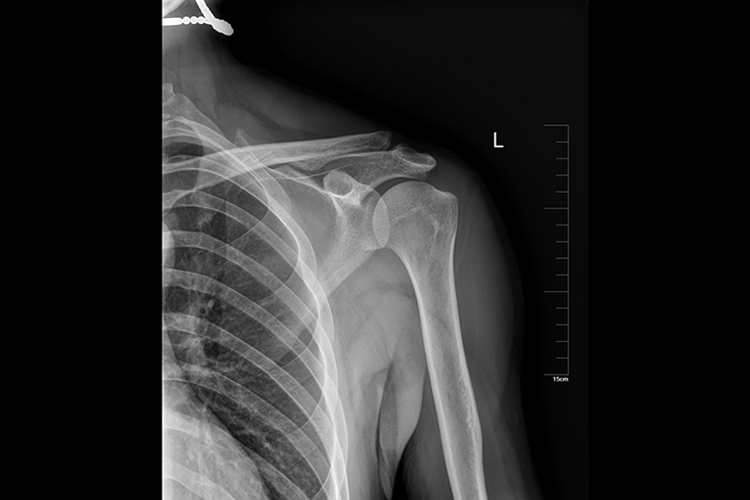

肱骨正侧位标准片,图像范围包括肱骨大结节、三角肌粗隆等,肱骨骨纹理清晰显示,软组织显示良好,常用于明确病位等。

肱骨的正侧位标准片表现为肱骨大结节位于其上端外侧缘,肱骨头与关节孟有少部分重叠,中段的三角肌粗隆位于骨干外侧,肱骨下端内、外上髁轮廓分别位于内外侧缘。肱骨骨纹理清晰显示,软组织显示良好。

肱骨正侧位标准片,主要用于判断病变的有无,观察病变的进展,证实或核实初步诊断,并明确病变的位置、大小、形状、性质等,或者指导骨折和脱位的整复、牵引固定和其他治疗措施等。